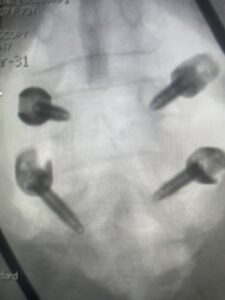

Fig 3: Lateral and AP fluoroscopic images demonstrating placement of pedicle screws for L4-5 fusion for spondylolisthesis.

Fig 6: AP and lateral fluoroscopic images demonstrating pedicle screw placement in L3-4 fusion for spondylolisthesis.